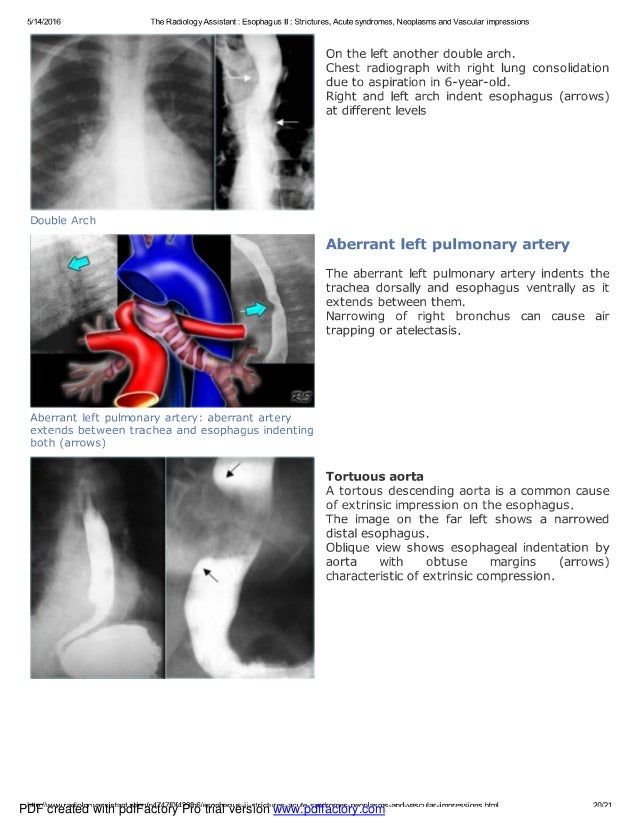

Chest x ray esophagus part ii